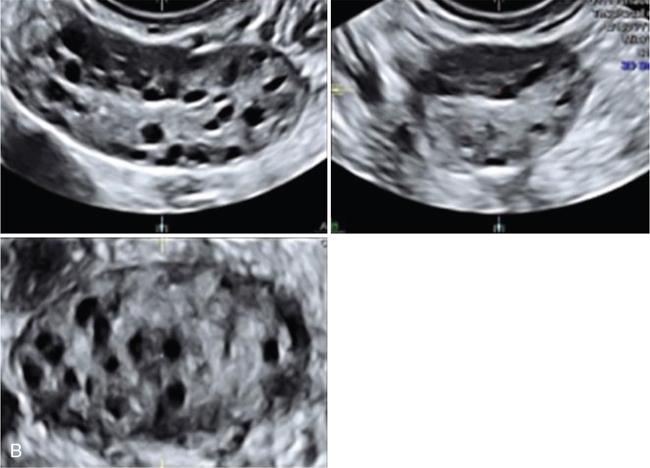

3. 3. 3D manual mode – reproducibility is better compared with 2D methods (Fig. 11.20.1.3).

• Allowing the use of rendering mode with thin slice, on contrast enhancement, making it easier to identify follicles

Image

Fig. 11.20.1.3 (A) 3D multiplanar mode without vocal contrast imaging (VCI). (B) 3D multiplanar mode with vocal contrast imaging (VCI).